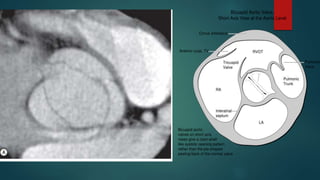

Tricuspid valve

disease

This valve has three leaflets

and three papillary

muscles, which partially

insert on the septum (in

contrast to the papillary

muscles of the mitral valve,

which do not)

Diseases